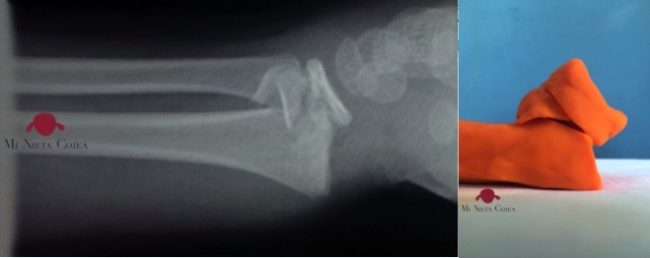

Una curiosidad saber el peso de una escayola. Pero si tu hijo tiene un problema nutricional y controlas bien el peso, es importante saber el cambio de peso que es culpa de la escayola. La escayola de la foto corresponde un “botín” de yeso, es decir por debajo de la rodilla, de un…